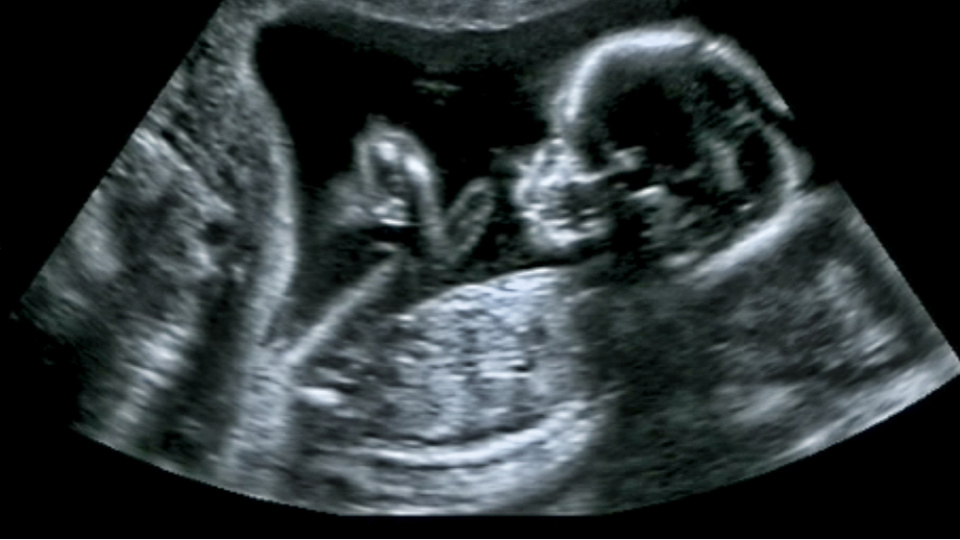

Sağlık Bilimleri Üniversitesi (SBÜ) Antalya Eğitim ve Araştırma Hastanesi (EAH) Kalp Damar Cerrahisi Ana Bilim Dalı Öğretim Üyesi Prof. Dr. Ali Ümit Yener, kalp ve damar sağlığının anne karnında başlayıp, ölüme kadar devam eden bir süreç olduğunu ifade etti.